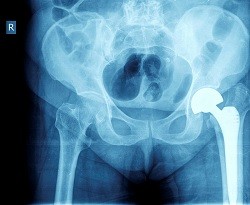

Prognostic factors for progression of osteoarthritis of the hip: a systematic review

In this systematic review, Teirlinck et al assess the existing evidence of patient, health, and diagnostic variables associated with the progression in patients with hip osteoarthritis.